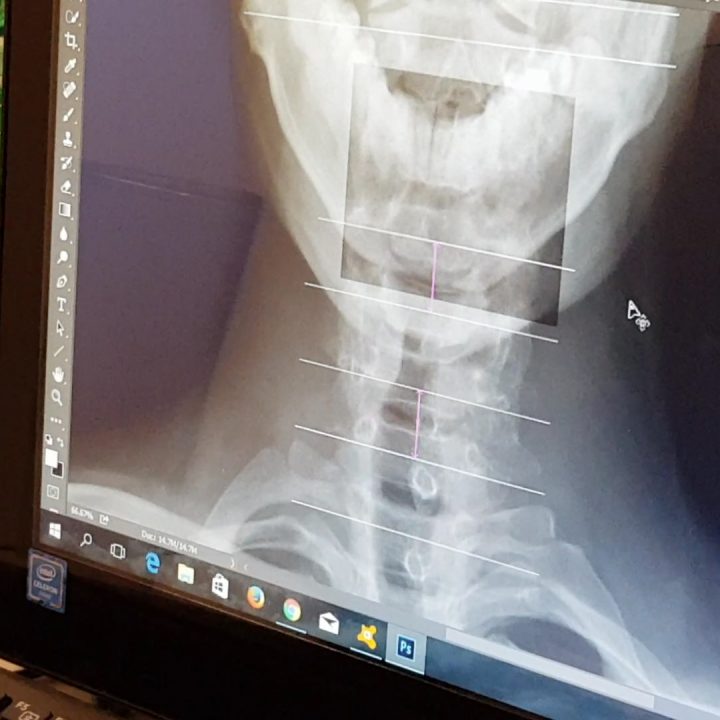

I personally like the way how Mabuhay Chiropractic Clinic handled new patients. The process starts with a full spine X-Ray, a personal history interview and physical check. Together, the doctor was able to accurately assess and confirm the source of the pain, why there is pain and how to adjust it accordingly… no guessing.